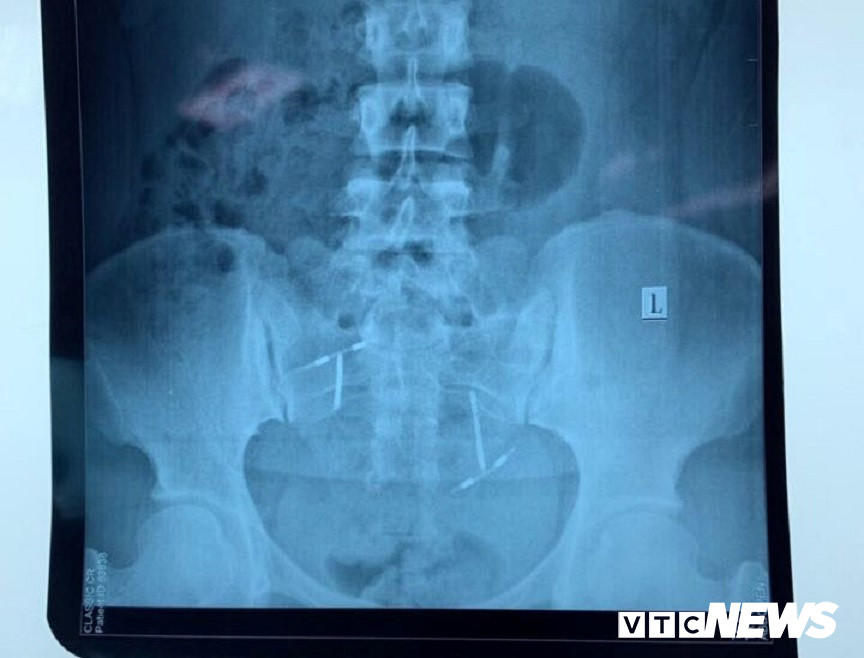

Vòng tránh thai "đi lạc" trong bàng quang của chị L.

Sau khi thực hiện các xét nghiệm thăm dò, chụp CT, chụp X-quang, hội chẩn các chuyên khoa…, các bác sĩ phát hiện dị vật nằm trong bàng quang của chị L.